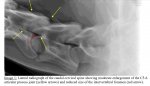

This is the xray from the report from my vets... I didn't even realise it was at the bottom of the report until my OH pointed it out! Just for information if anyone is interested really:

View attachment 54290